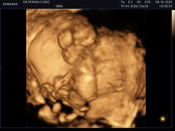

เค้าก็ขึ้นแบบในรูปค่ะ ตอนนี้ได้12วีคแล้ว 🤣

ของบ้านนี้จางกว่านี้ค่ะ ตอนนี้21+3wแล้วต่ะ

แบบนี้ถือว่าเข้มเลยค่ะ ท้องแน่นอน

อันนี้ไม่จางนะคะ ค่อนเข้มเลยค่ะ

ไม่จางนะแม่ชัดเลย ท้องค่ะ

ของเราจางกว่านี้ ท้องค่ะ